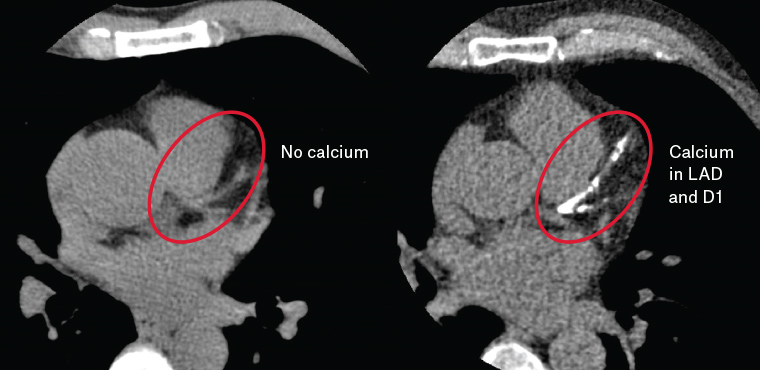

calcium coronary artery lad arteries prevention primary left anterior descending racgp scores d1